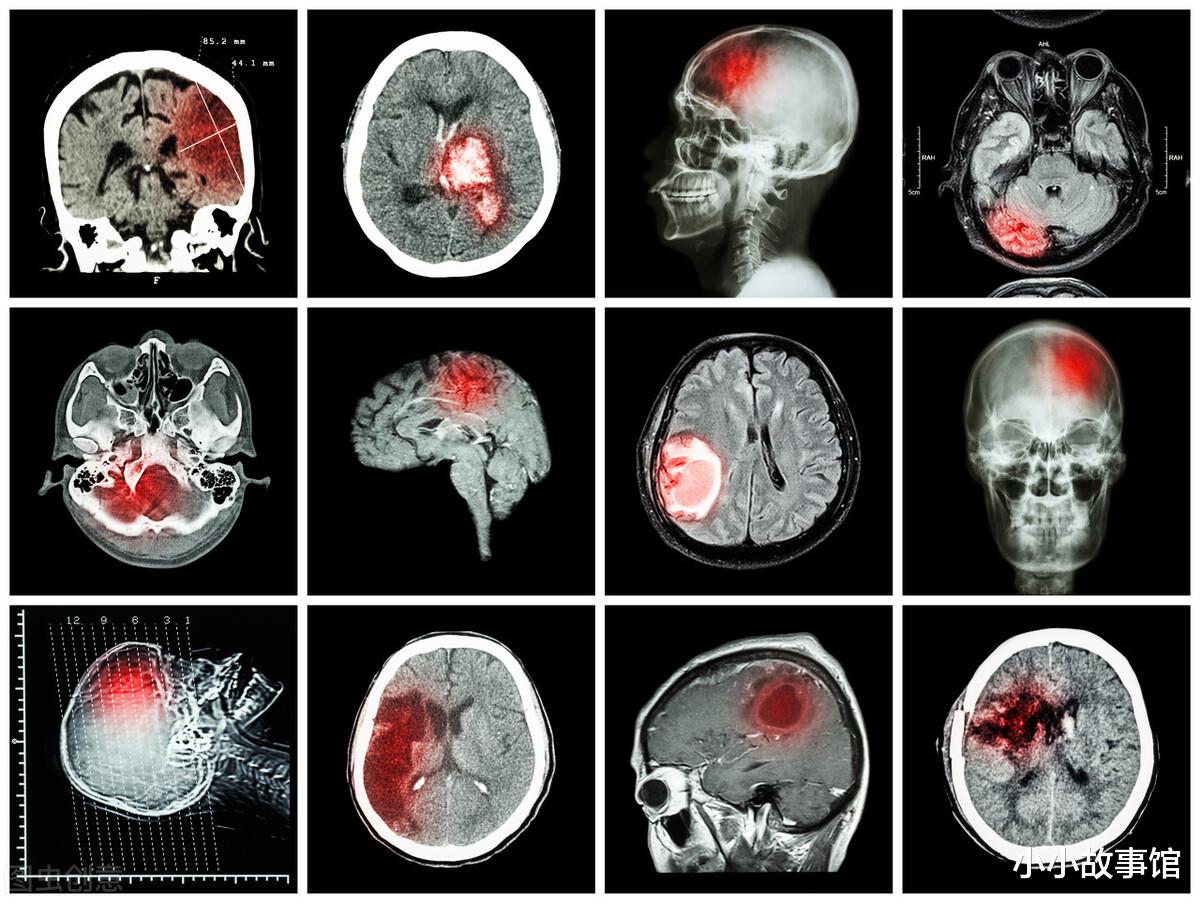

医生抽血检查发现 , 赵大爷甘油三酯和胆固醇的含量都非常的高 , 低密度脂蛋白含量也远高于正常水平 , 又再次给赵大爷进行了脑CT扫描发现大脑的动脉处仅有局部血栓形成 , 这说明他患有脑梗 , 如果不及时进行治疗 , 后期很有可能会导致生命危险 。